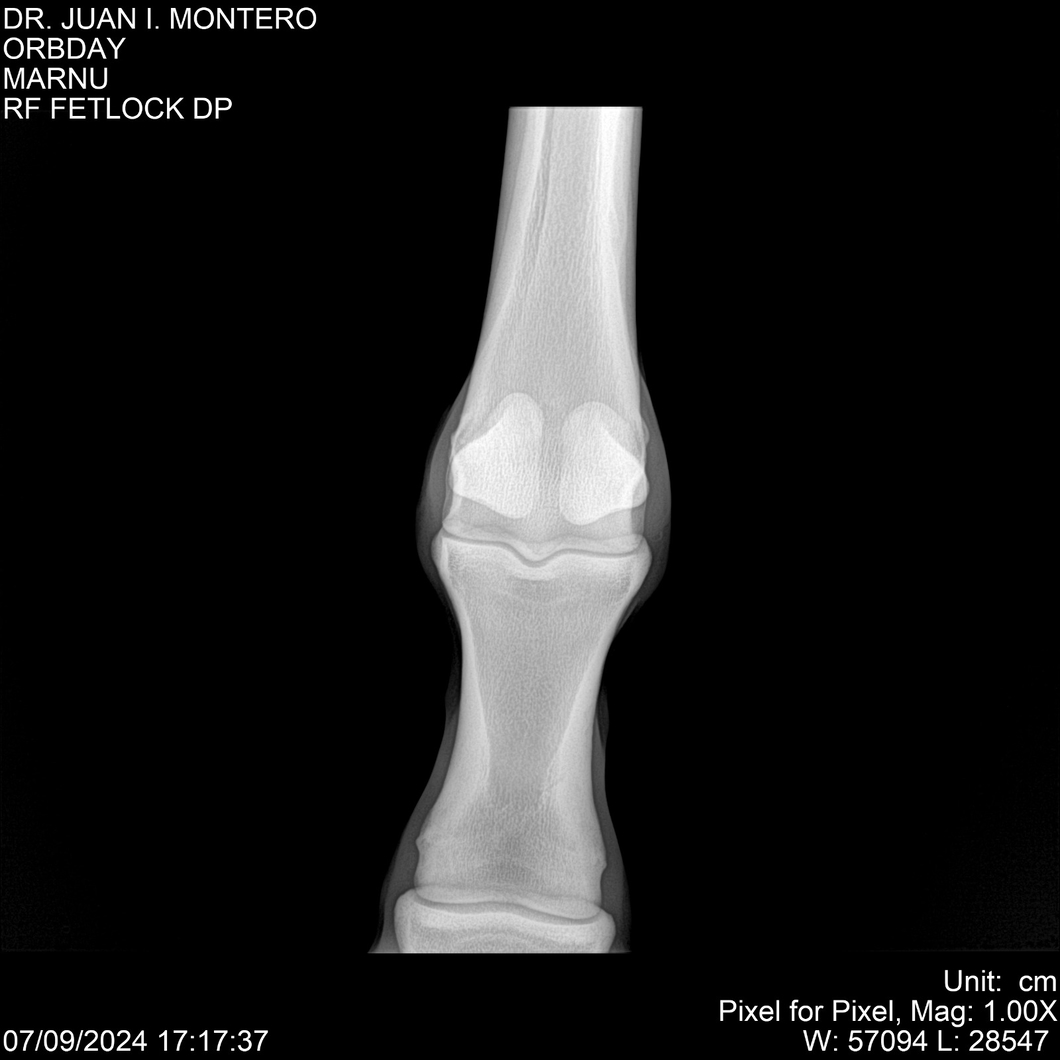

• Empresa: Abelenda N. R., Walter Hugo